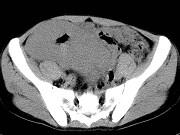

问题 男,23岁,下腹部肿块伴持续性钝痛1月余,影像所见如图,最可能的诊断是()

选项 A.小肠淋巴瘤 B.小肠间质瘤 C.小肠癌 D.小肠转移瘤 E.小肠结核

答案 A